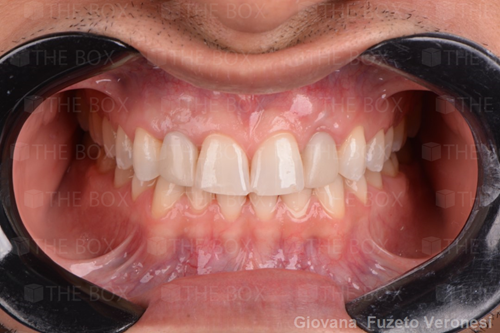

A new case was made public by Jean-Claude Imber check it out here.